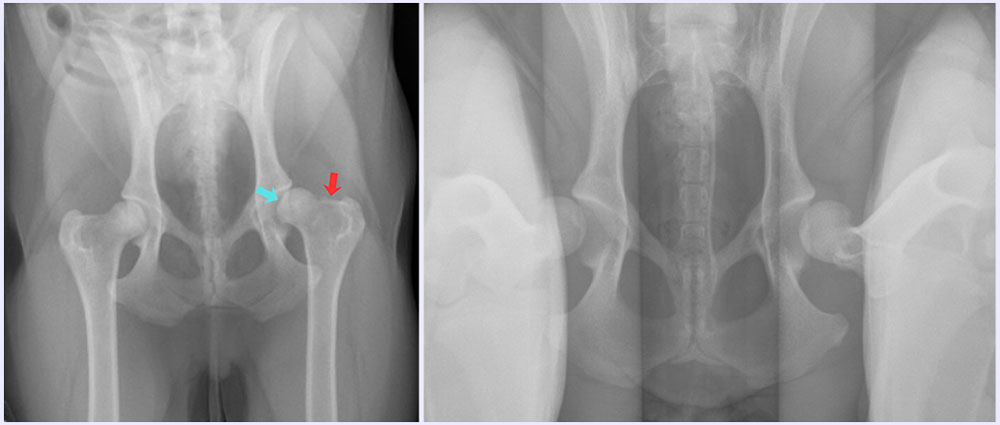

The first picture is a standard extended-leg view of the pelvis – at a quick glance they don’t look too bad. Closer inspection shows the left femur (on the right side of the picture) is a little flattened (blue arrow) and not sitting as well within the hip socket, as well as some small osteophytes (bone spurs characteristic of osteoarthritis) forming on the neck of the femur (red arrow).

The second picture is the Penn-Hipp, and here you can really see just how far the femoral heads can move outside of the hip socket, and that calculated amount of movement is called the “Distraction Index” (DI). The average DI for Australian Shepherds is 0.47, meaning the breed is generally at a moderate risk of hip arthritis due to hip dysplasia. OK’s DI was 0.85!! This means that he was at very high risk of developing arthritis – and, in fact, the x-rays showed he already was!